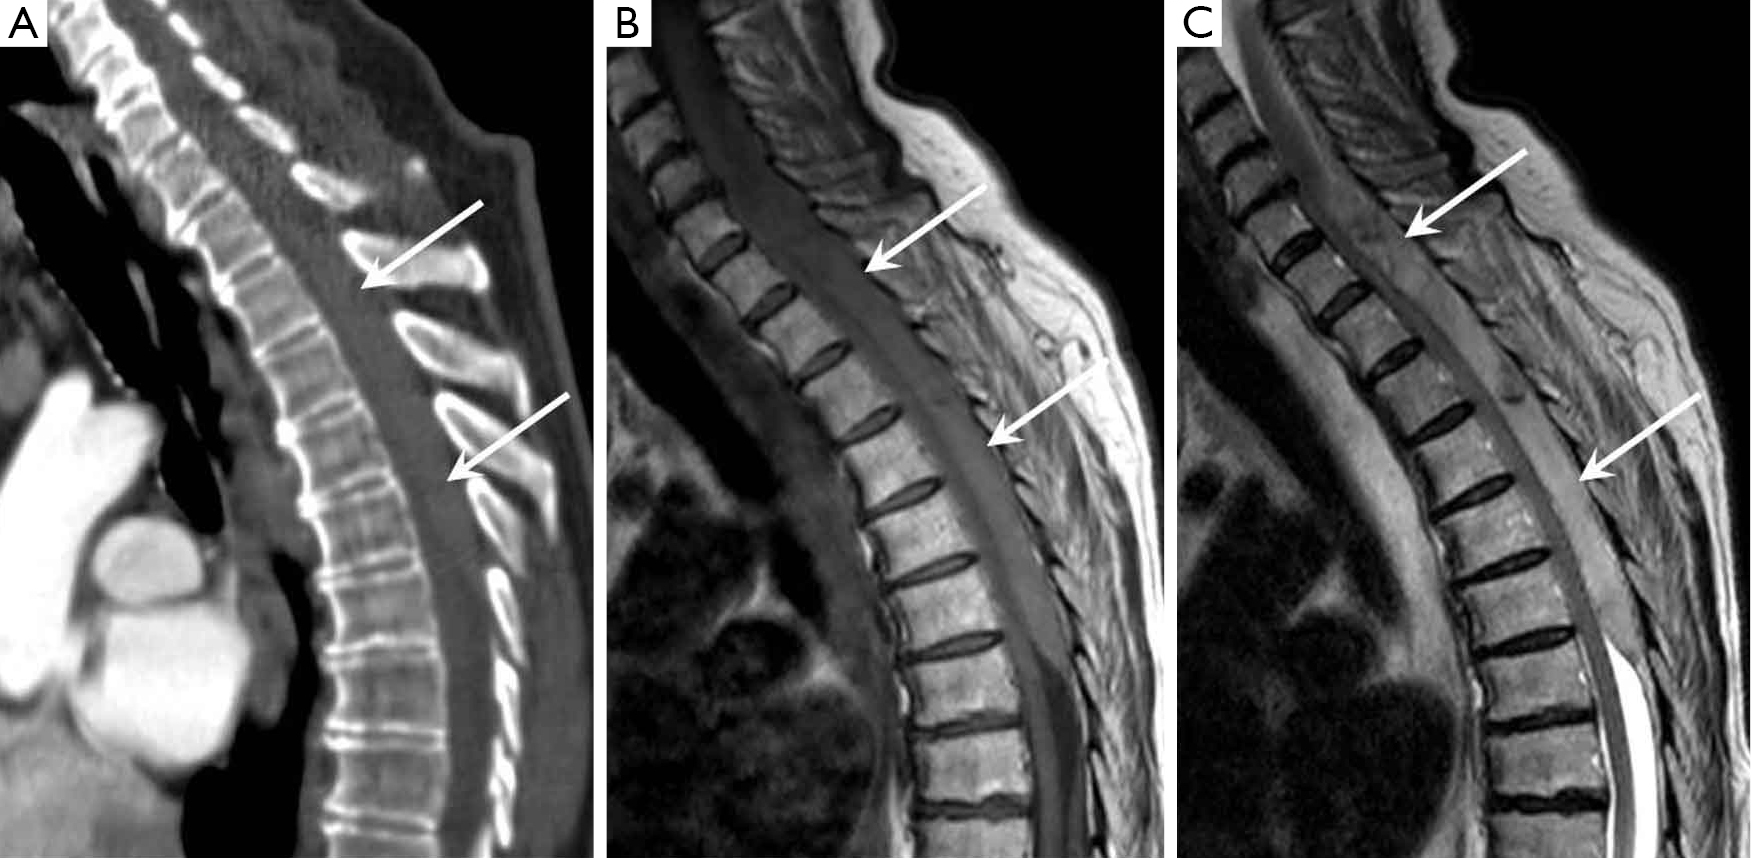

From www.cureus.com

Cureus Catheterbased Minimally Invasive Evacuation of Extensive Epidural Catheter Mri Safety Find out the imaging limitations, artifact issues, and heating risks of different types of hardware and how to prepare for the scan. a panel of radiologists from nine academic centers provides 36 recommendations on mri safety issues for 10 common. learn about the mr safety of different types of epidural catheters, including duraflex and duraflex plus. epidural. Epidural Catheter Mri Safety.